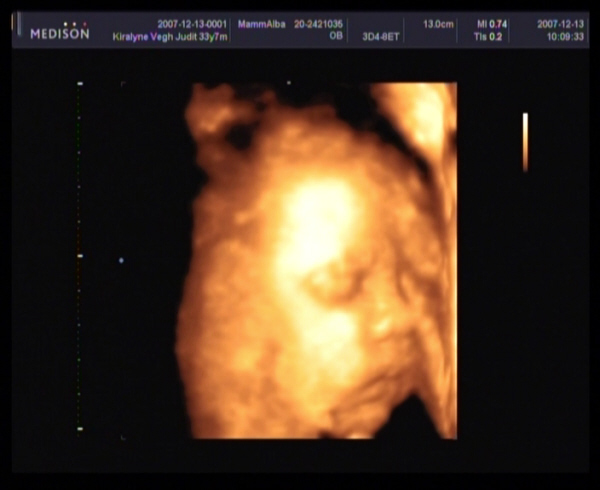

26 hetesen2007.12.13 20:04